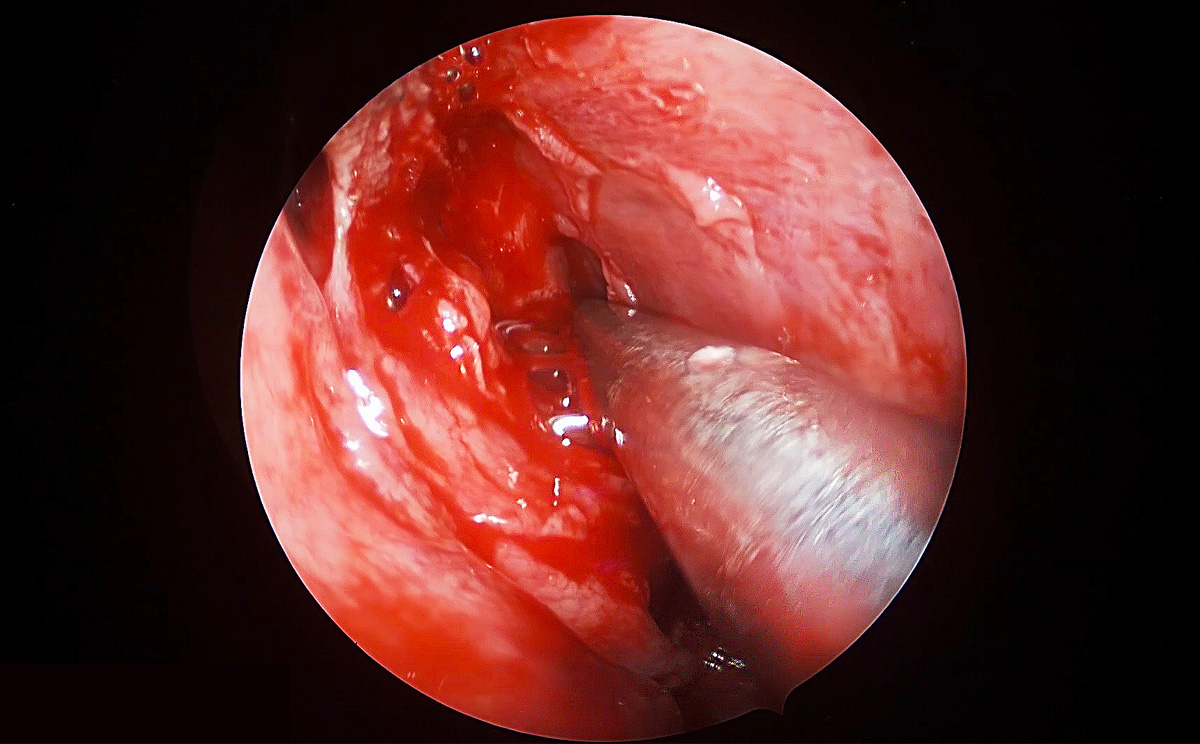

4K超高清內窺鏡攝像系統在腦垂體瘤切除術中的精彩表現

此次手術采用內窺鏡下經鼻進路行腦垂體瘤切除術,使用機器益柯達4K超高清內窺鏡攝像系統,分辨率可達3840X2160P,是全高清內窺鏡分辨率(1920X1080P)的4倍,該產品具有出色的色彩還原功能,能夠精細的顯示手術中的細微血管、神經、筋膜層次,使手術更精準、安全。